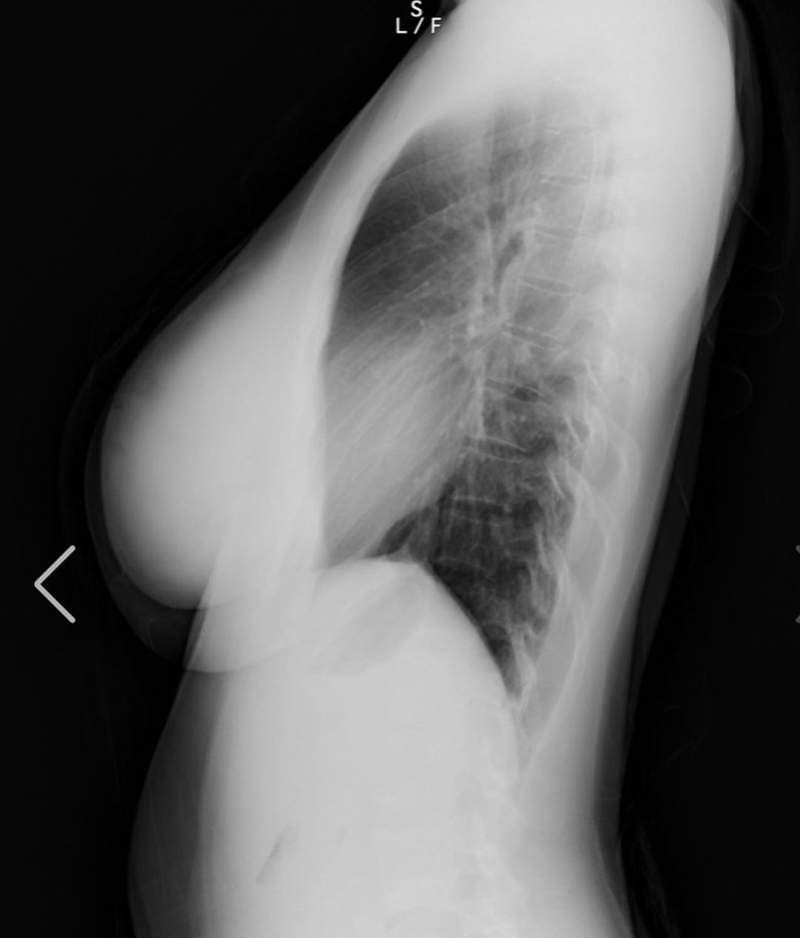

至于今天开头跟大家分享的上空X光照,大家千万不要觉得阿漆又要唬烂骗点阅,实际上她在最近真的有公开自己的X光照片,其实她在之前8月的时候曾确诊新冠肺炎,休养一个月之后康复已经完全健康,现在做个体检也是确认不要有后遗症

另外之前有网友曾质疑她胸部作假,这么大肯定不是天然的胸部,而这次在社群媒体上公开自己的体检结果,也间接打脸掉这个说法,她的胸部没有任何填充物,而右胸上小小的黑点是胃泡,所以整体检查结果下来是很OK的